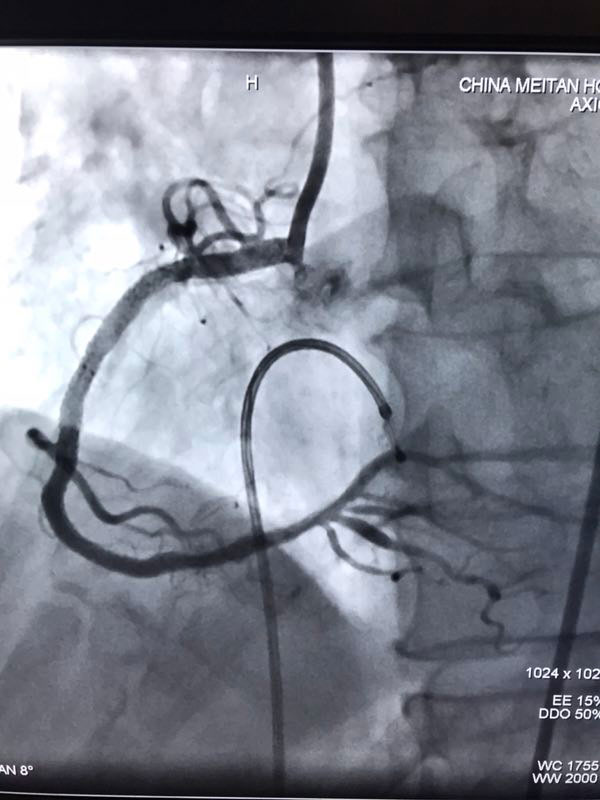

据了解,三位患者都是因严重心绞痛和非ST心梗入院,最高年龄88岁,另两名也有70多岁,是普通PCI难以治疗的危重患者。其中两名已辗转多家医院,均未得到有效救治。患者转入我院后,我院心内科在吴迪主任的带领下,经过周密的准备和科学评估,在血管内超声和临时起搏的辅助指引下,圆满完成了三台旋磨加PCI手术,术后IVUS显示治疗部位支架充分覆盖贴壁,彻底解决了三位患者的病痛,改善了长期预后。

据吴迪主任介绍,冠脉钙化病变和慢性闭塞病变一直是冠心病介入治疗的两大难题,特别是占20%比例的钙化病变,极大的难度风险及高并发症低成功率对心脏介入医生而言是巨大的壁垒和挑战。冠脉旋磨技术作为国家临床二类新技术,就是针对复杂严重钙化病变,通过特制的金刚石探头,在导丝指引氮气加压推进下送入冠脉,借助每秒高达17万转的高速旋转将钙化部位磨平断开,然后借助切割球囊分解斑块,为最终顺利植入支架创造条件。